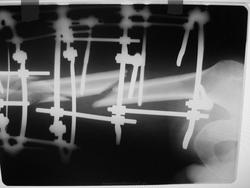

snimki_004..jpg

Консолидация есть. Присмотритесь. Между правым отломком и осколком образовался костный мостик.

Ответье пожалуйста, пациент нагружет каким-то образом эту конечность?